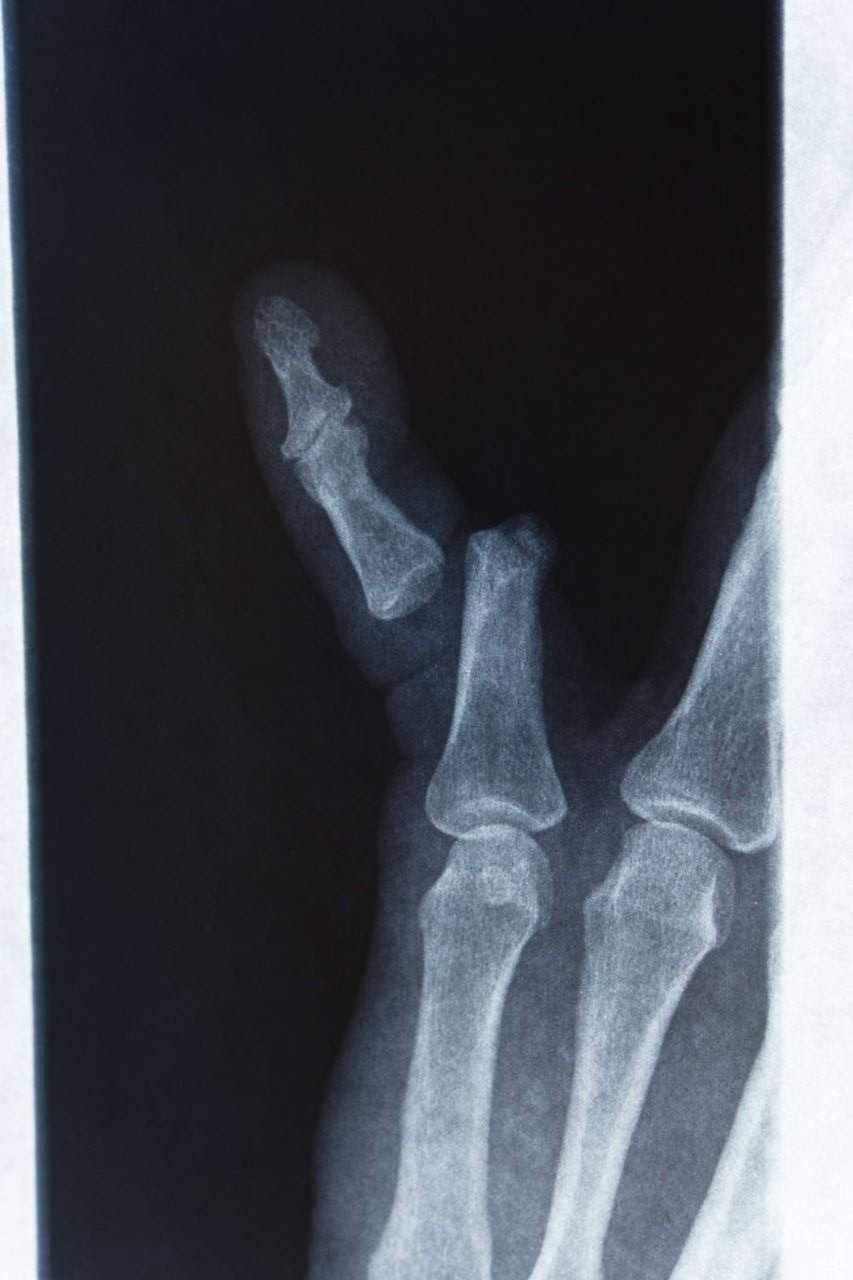

발가락 골절은 말 그대로 발가락 뼈(지골)에 금이 가거나 완전히 부러지는 상황을 뜻합니다. 일상 속 작은 충격부터, 스포츠 활동 중 강한 타격까지 다양한 원인으로 생길 수 있습니다. 특히 발가락 끝이 가구에 부딪히는 사소한 실수로도 골절이 발생할 수 있어, “정말 작게 다쳤는데 의외로 크게 아프다”라는 말을 자주 듣게 됩니다.

골절 유형

- 단순 골절: 뼈가 한 번 금이 가거나 깨진 정도로, 비교적 뼈 조각이 많이 어긋나지 않은 경우입니다.

- 복합 골절: 뼈가 여러 조각으로 나뉘거나, 뼈가 제 위치에서 크게 어긋난 경우입니다.

- 압박 골절: 압력에 의해 납작하게 뭉개지듯 부러진 형태이며, 골절 부위가 복합적으로 손상되기 쉽습니다.